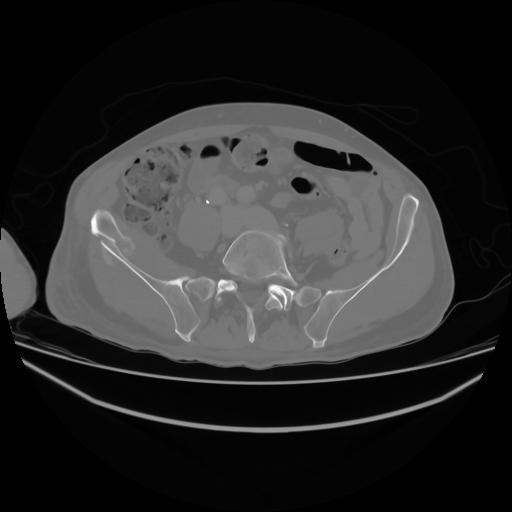

4 CUERPO,CE,Axial,3.0,CUERPO,,